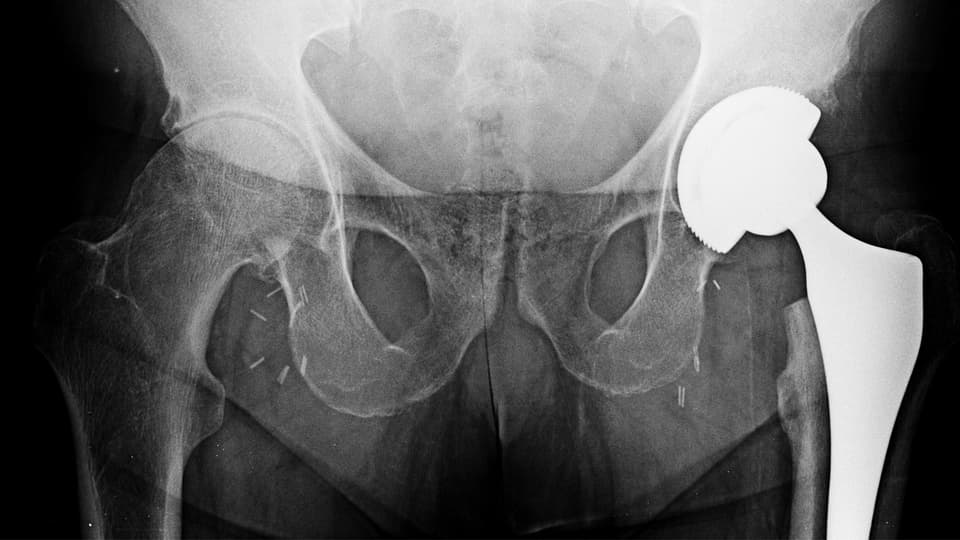

Мрт тазобедренного сустава в минске